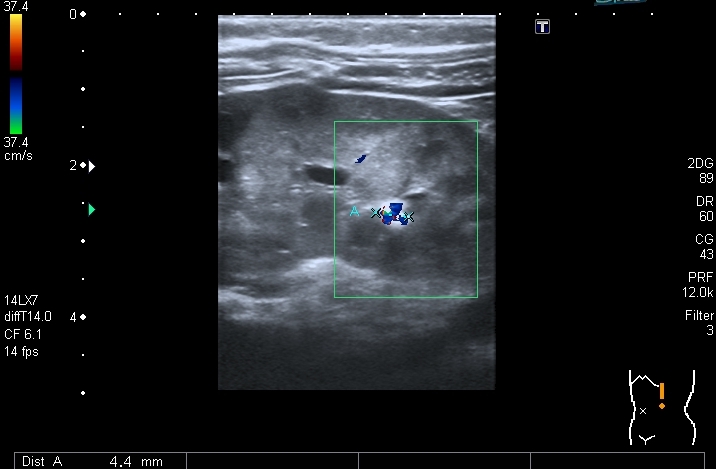

В нижней чашечке левой почки - конкремент до 5 мм

Конкремент даёт твитлинг - артефакт

В мочевом пузыре определяется достаточно большое уретероцеле слева, периодически увеличивающееся и пульсационное уретероцеле справа. Левый мочеточник в нижней трети резко расширен.